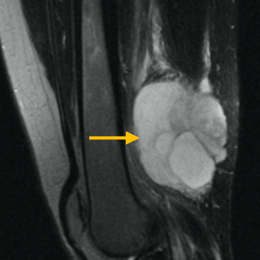

Radiographic imaging is used to help form a diagnosis of pleomorphic liposarcoma. These include X-Ray, MRI, CT and Bone Scans

An example of an MRI is shown.